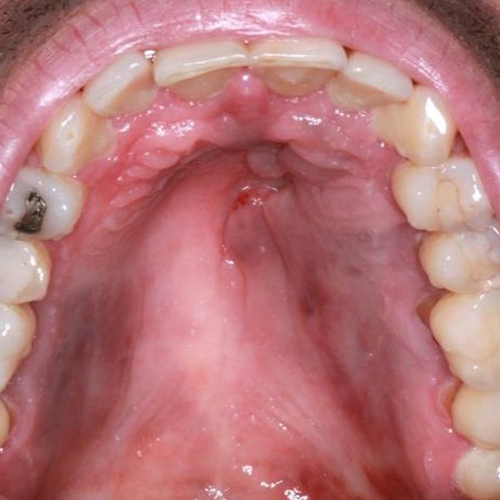

۹) اسکواموس پاپیلوما: یک ضایعه برجسته روی مخاط دهان است که محصول پرولیفراسیون خوشخیم سلولهای اپیتلیالی میباشد. علت آن ویروس پاپیلومای انسانی (HPV) است.

شایع ترین مکان آن مرز کام نرم و سخت است.

رنگ آن اغلب سفید و گاهی صورتی است. خیلی بزرگ نمیشود و صد البته در جوانان بیشتر رخ میدهد.

تصاویری از تومورهای دهانی